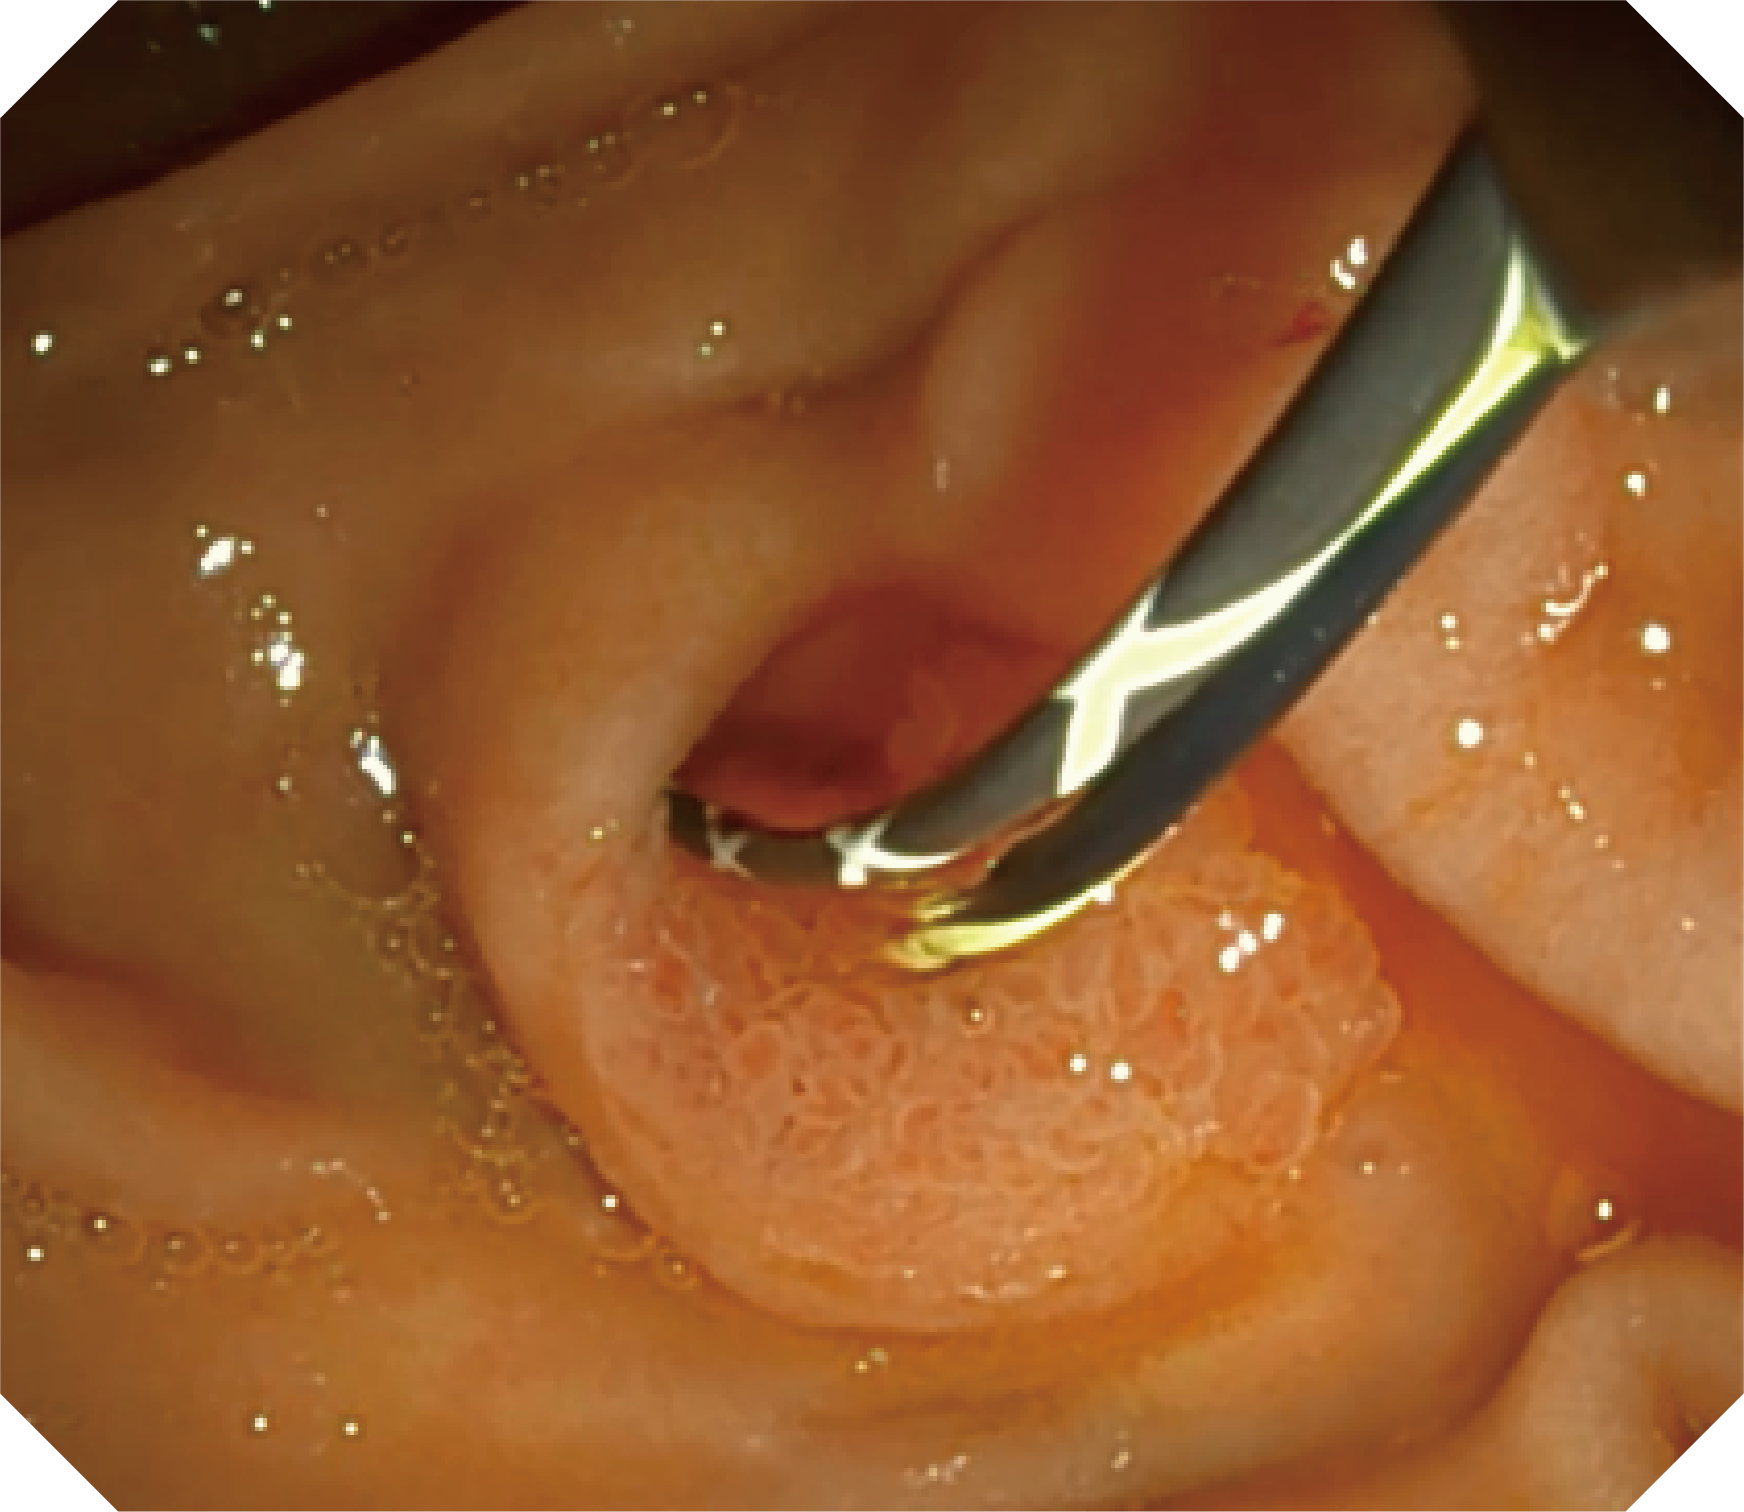

CMOS传感器提供高清内镜视野 SFI/VIST光学染色技术凸显病变区域

可拆卸先端帽

4.2mm大钳道,器械交换更顺畅

优异的手术器械抬举性